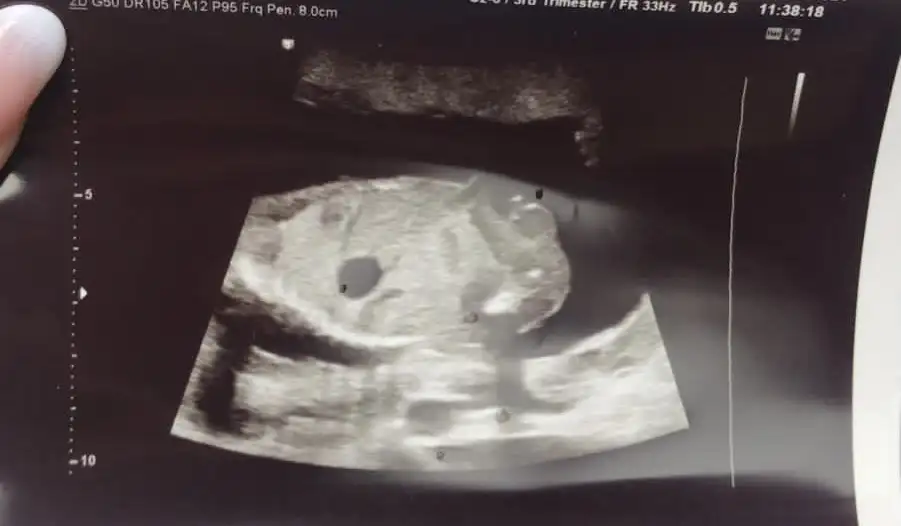

Arkadaşlar selam bizde çok kız bebek istiyorduk 12. Ve 14. Haftalarda doktorumuz kız demişti ama bugun 16.5 haftalık kontrolümüzde yanıldım diyerek erkek olduğunu söyledi ultrason fotoğraflarını paylaşıyorum ne düşünüyosunuz